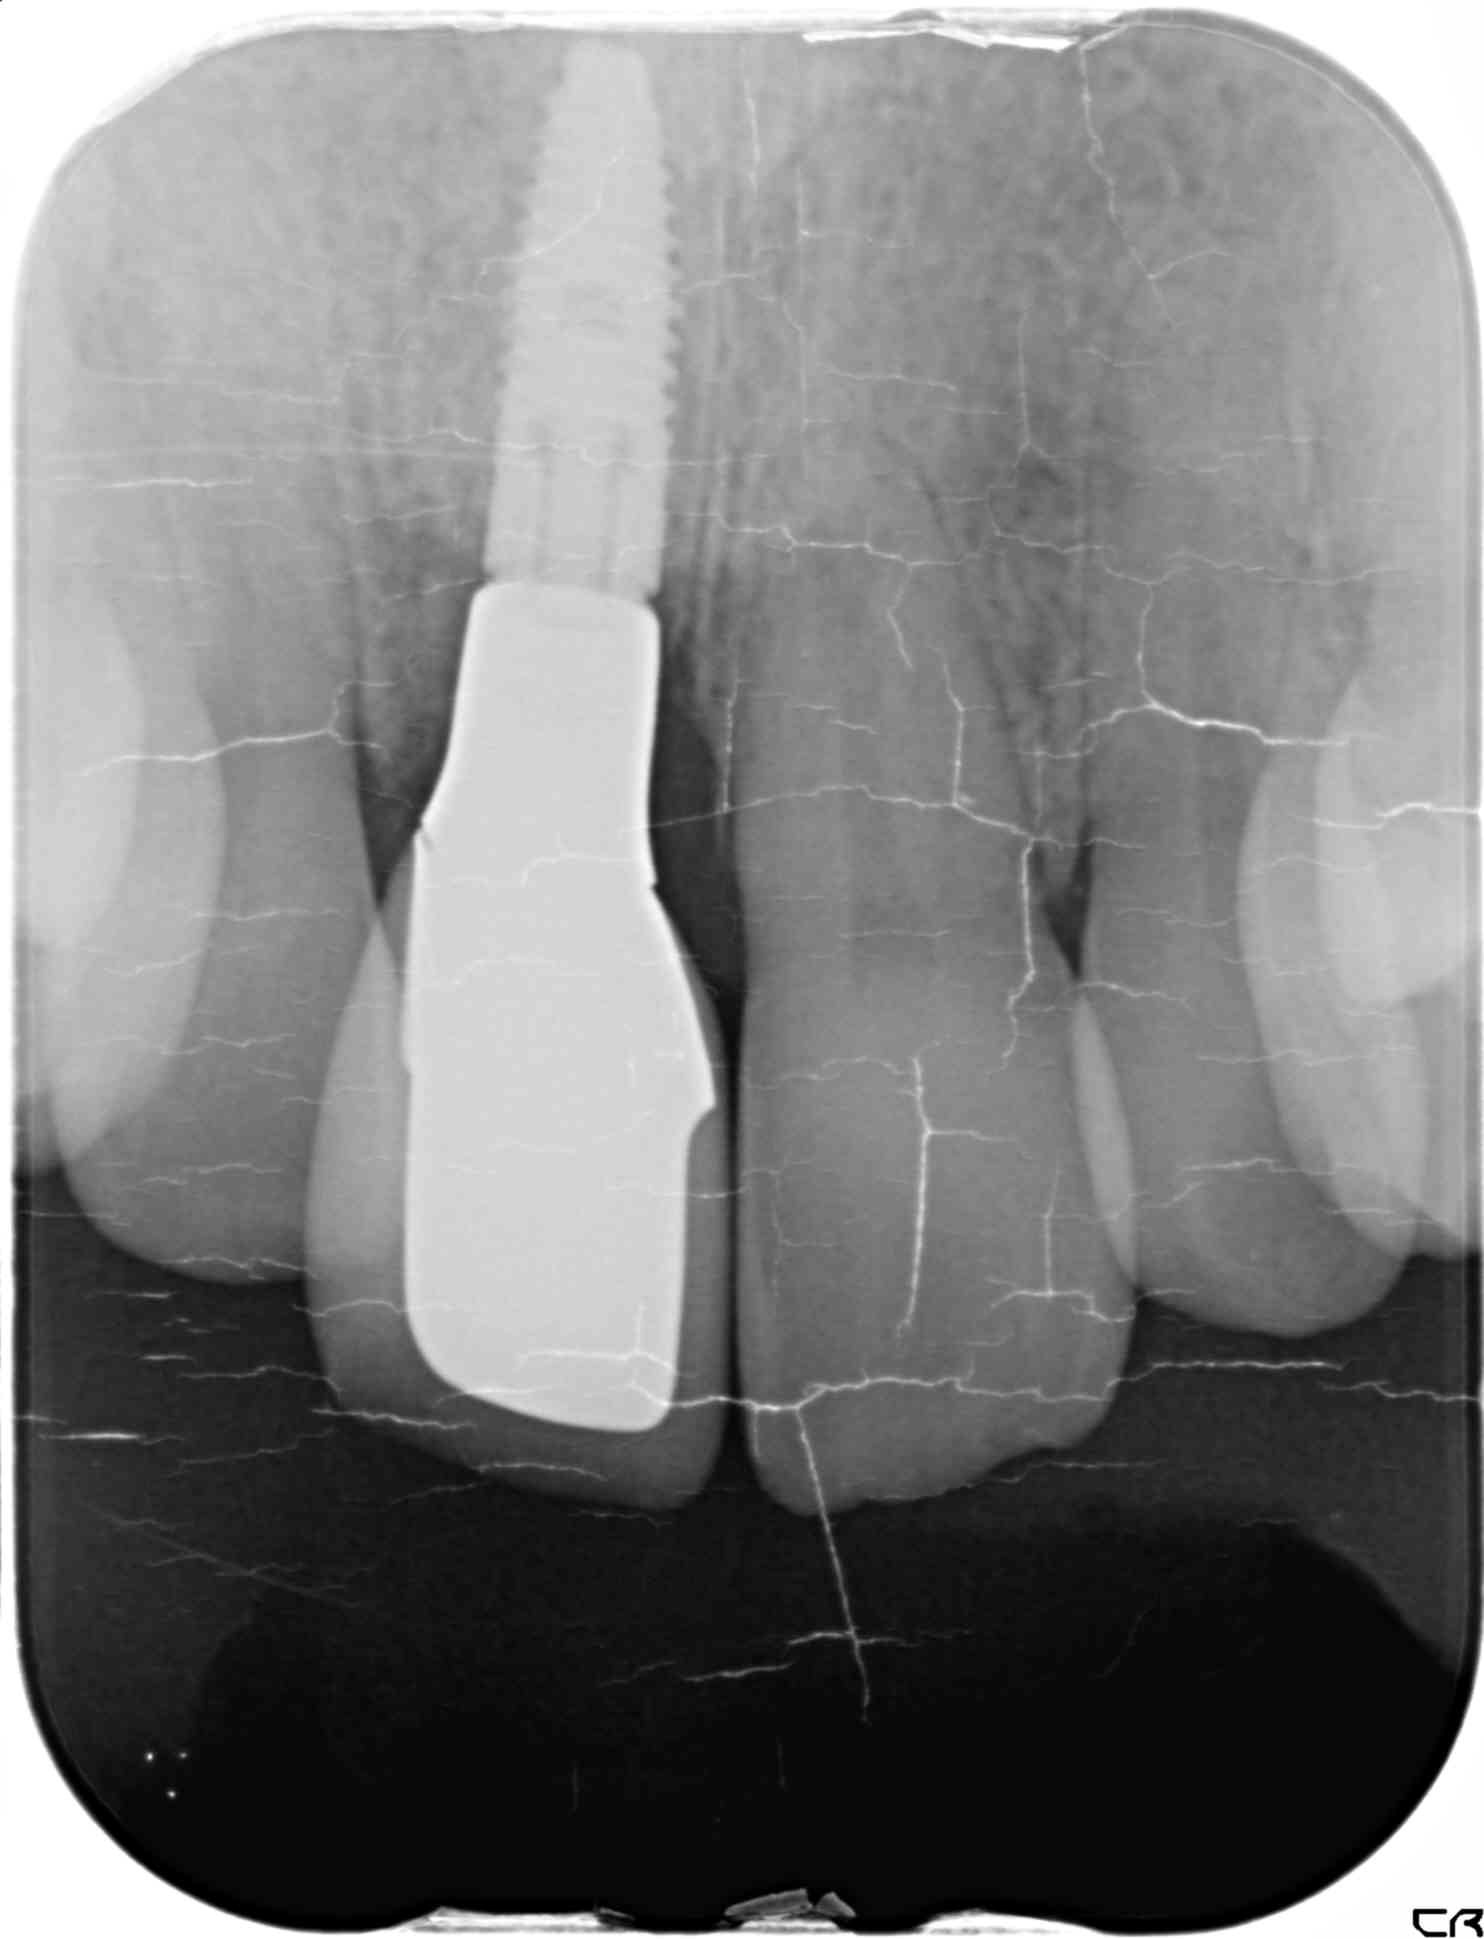

【レントゲン写真】

※下記写真はインプラントの被せ物が入った術後のレントゲン写真

抜歯後は骨の幅が不足していたため、骨造成(GBR)を併用し、約半年後にインプラント治療を行いました。

治療に使用したかぶせ物(人工歯)はオールセラミック製で、自然な透明感があり、変色しにくい素材です。また、清掃性が高いとされており、プラーク(歯垢)が付きにくい特徴があります。